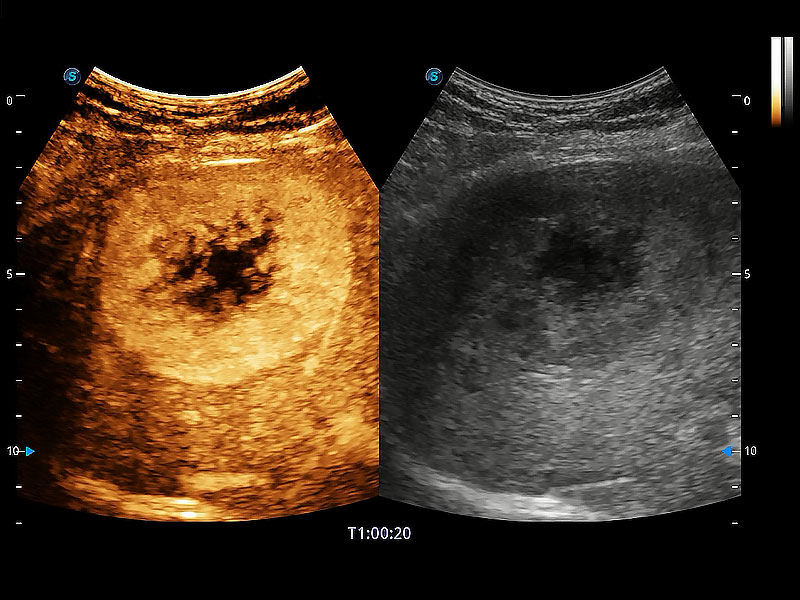

在传统二维血流成像的基础上,呈现血流的立体感,具有动感的生命力之美。即便是微小的血管也能轻松应对,提高了血流的视觉敏感性。